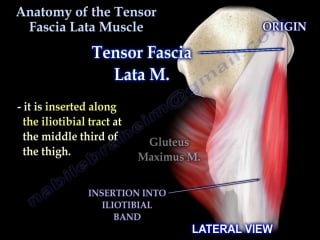

Anatomy of the tensor fascia lata muscle everything you need to know dr nabil ebraheim